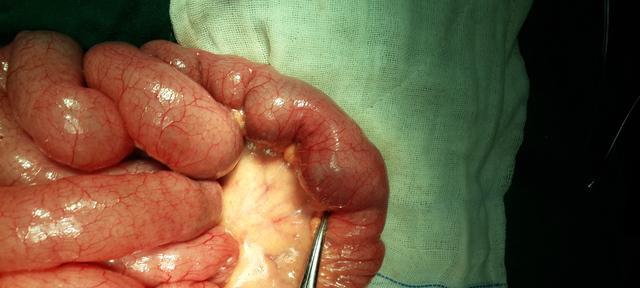

狗肠梗阻是一种常见的狗病,若不及时治疗,可能会导致宠物生命危险。对于确诊为狗肠梗阻的宠物,手术是常见的治疗方式。然而,许多宠物主人对手术后的恢复时间和注意事项存在疑问。本文将详细介绍狗肠梗阻手术后的恢复时间及加速康复的方法,以帮助宠物主人更好地照顾和照料宠物。